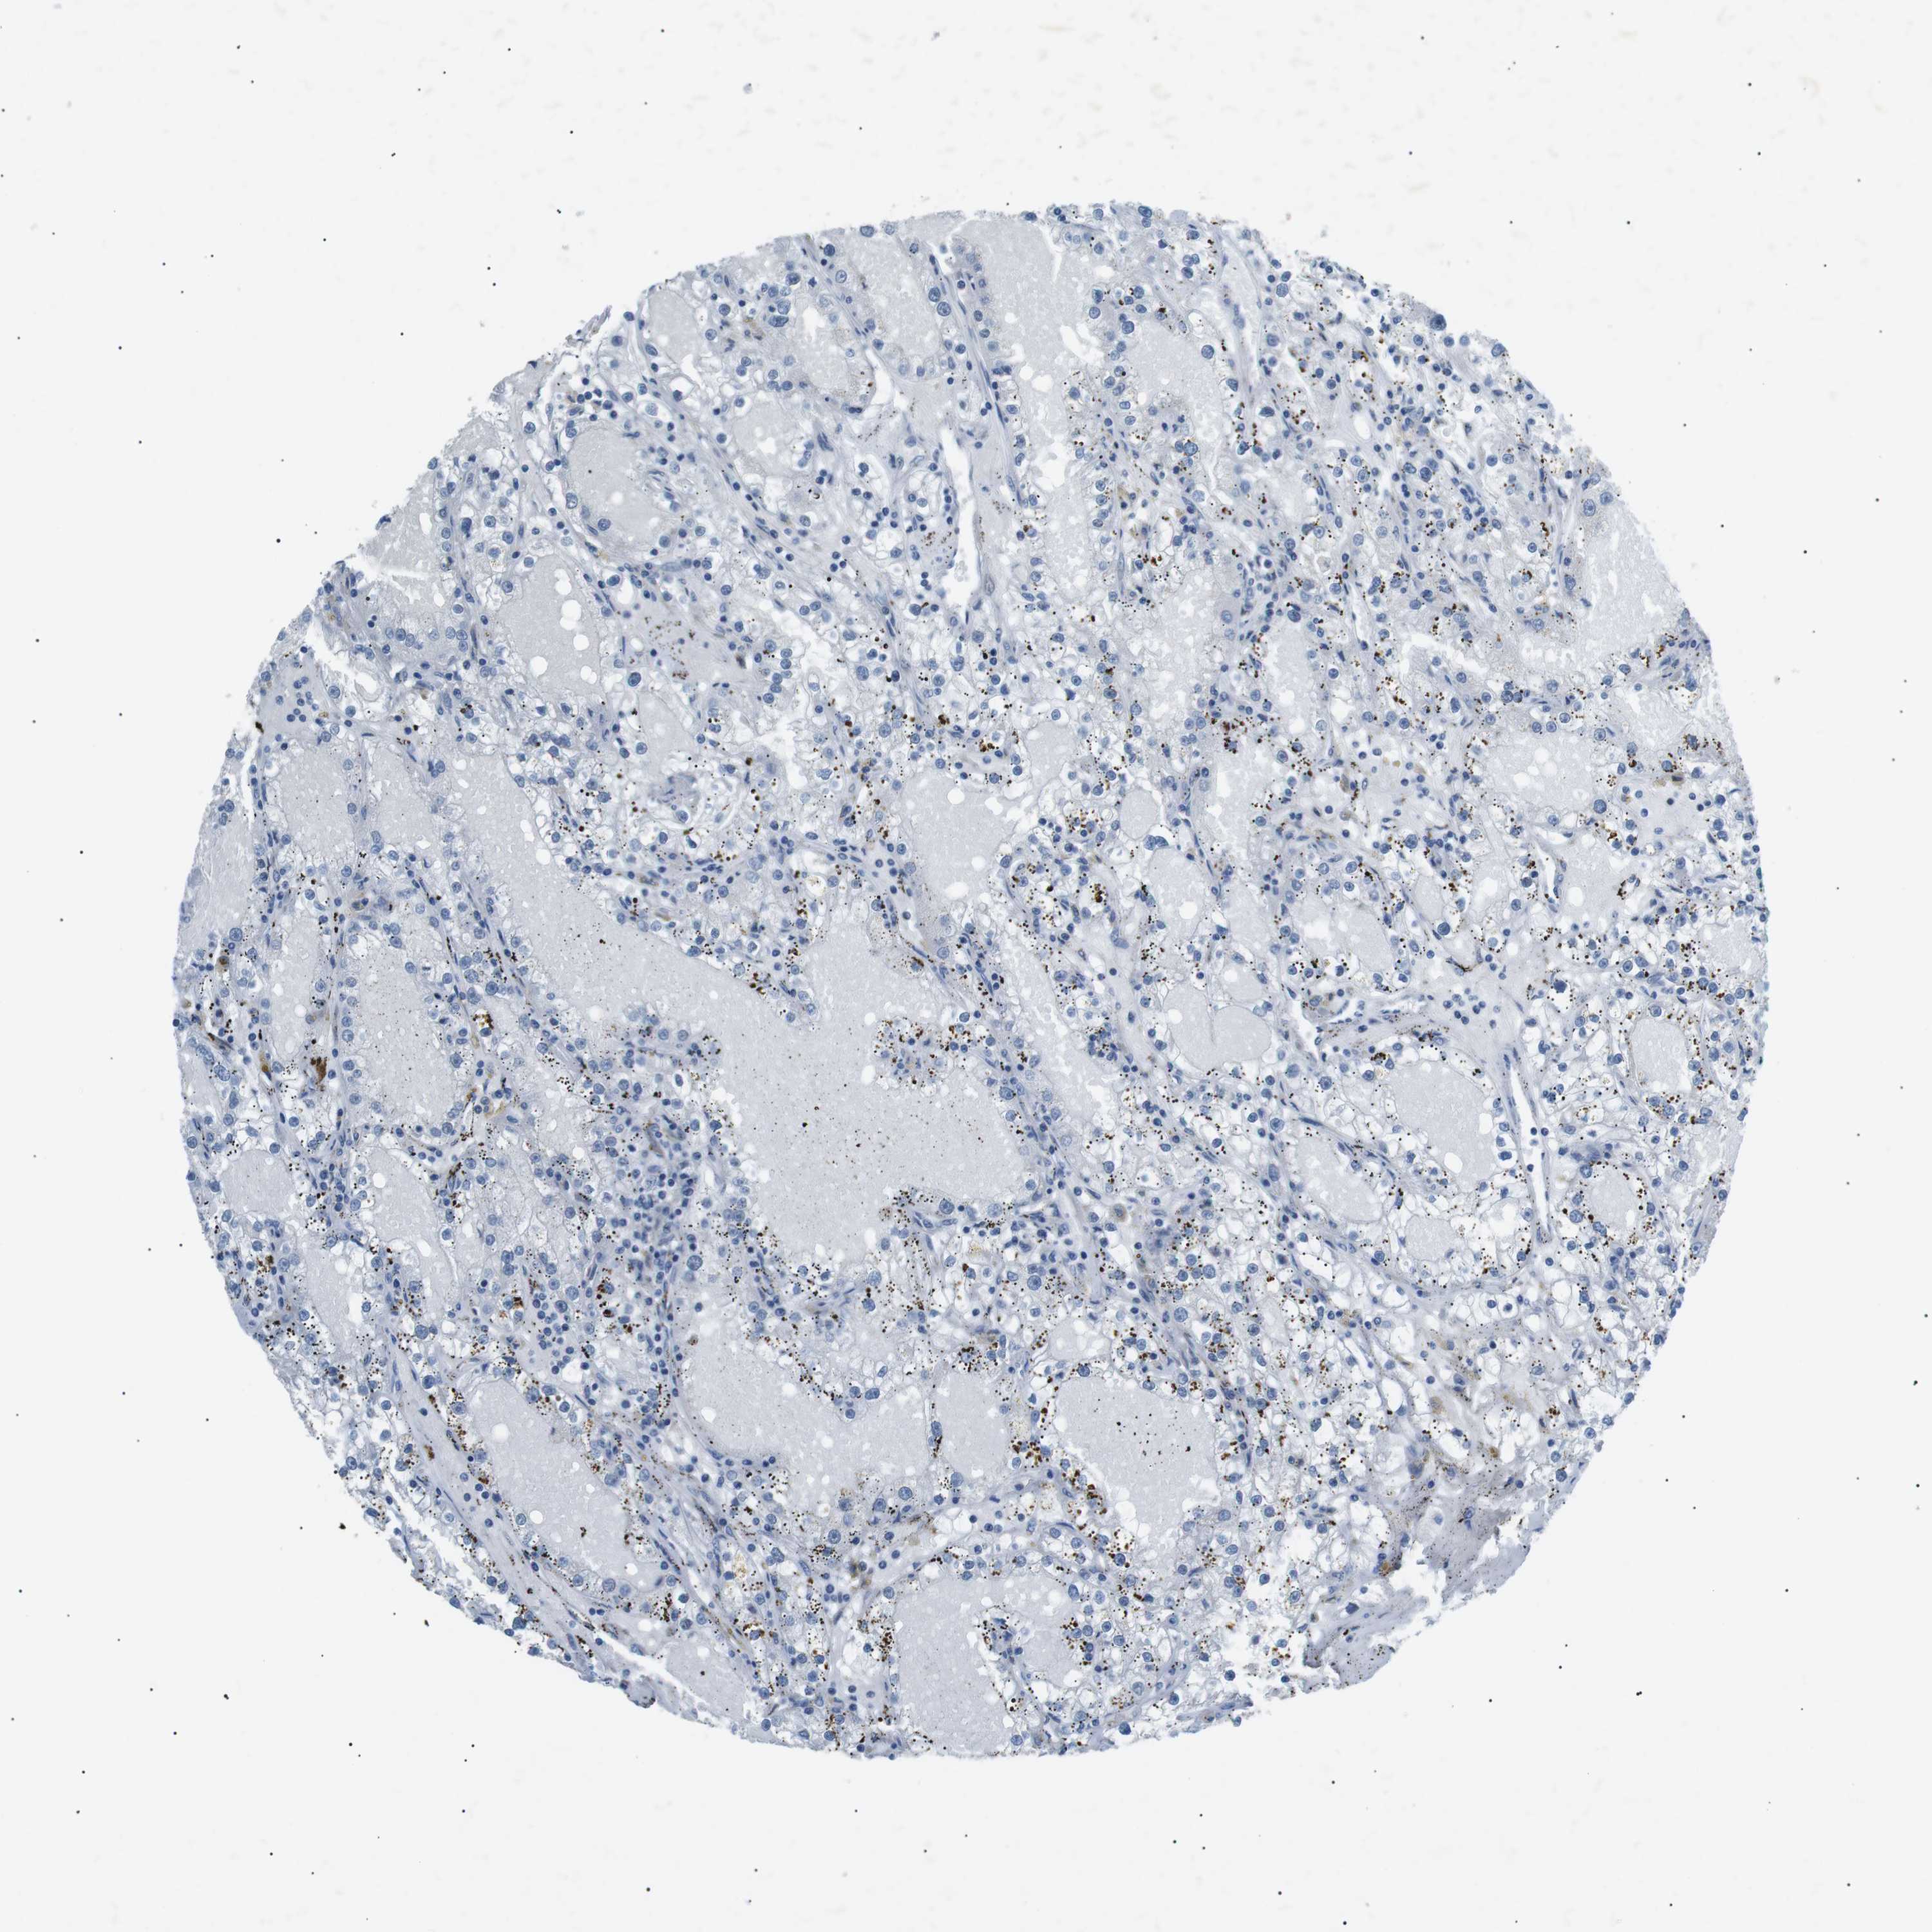

KIDNEY RENAL PAPILLARY CELL CARCINOMA (TCGA) - Interactive survival scatter ploti

The Survival Scatter plot shows the clinical status (i.e. dead or alive) for all individuals in the patient cohort, based on the same data that underlies the corresponding Kaplan-Meier plots. Patients that are alive at last time for follow-up are shown in blue and patients who have died during the study are shown in red.

The x-axis shows the expression levels (FPKM) of the investigated gene in the tumor tissue at the time of diagnosis. The y-axis shows the follow-up time after diagnosis (years). Both axes are complimented with kernel density curves demonstrating the data density over the axes. The top density plot shows the expression levels (FPKM) distribution among dead (red) and alive patients (blue). The right density plot shows the data density of the survived years of dead patients with high and low expression levels respectively, stratified using the cutoff indicated by the vertical dashed line through the Survival Scatter plot. This cutoff is automatically defined based on the FPKM cutoff that minimizes the p-score. The cutoff can be changed by dragging the vertical line or by entering a cutoff value in the square labeled "Current cut-off".

Under the Survival Scatter plot the p-score landscape (black curve; left axis) is shown together with dead median separation (red curve; right axis). Dead median separation is the difference in median mRNA expression between patients who have died with high and low expression, respectively. It is calculated as follows: median FPKM expression of dead patients with high expression - median FPKM expression of dead patients with low expression. This is intended to aid the user in visually exploring custom cutoffs and the associated p-scores and dead median separation.

Individual patient data is displayed and can be filtered by clicking on one or more of the category buttons on the top of the page. Categories describing expression level and patient information include: high, low, alive, dead, female, male and tumor stages. The scale of the x-axis can be toggled between linear and log-scale by clicking on the "x log" button. Mouse-over function shows TCGA ID, patient information and mRNA expression (FPKM) for each patient.

& Survival analysisi

Kaplan-Meier plots summarize results from analysis of correlation between mRNA expression level and patient survival. Patients were divided based on level of expression into one of the two groups "low" (under cut off) or "high" (over cut off). X-axis shows time for survival (years) and y-axis shows the probability of survival, where 1.0 corresponds to 100 percent.

ARID5B is not prognostic in Kidney Renal Papillary Cell Carcinoma (TCGA)